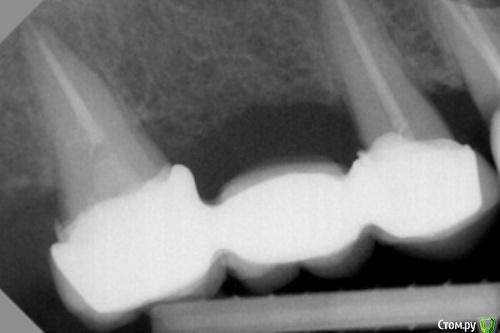

dr.Dre Опубликовано 25 сентября, 2017 Поделиться Опубликовано 25 сентября, 2017 Добрый день коллеги.Такая ситуация пациентка 50 лет 3 месяца тому поставили мк,все было нормально.Теперь обнаружил в промежуточной части с обеих сторон десна припухла,рыхлая .Перкусия зубов отрицательная ,что ето может быть? Ссылка на комментарий

dr.Dre Опубликовано 25 сентября, 2017 Автор Поделиться Опубликовано 25 сентября, 2017 Правая сторона пока только таие данные имею Ссылка на комментарий

dok1 Опубликовано 25 сентября, 2017 Поделиться Опубликовано 25 сентября, 2017 Ну ступени... чё. 2 Ссылка на комментарий

dok1 Опубликовано 25 сентября, 2017 Поделиться Опубликовано 25 сентября, 2017 Стык коронки с уступом. Поднутрения ну и дальше классически. Ссылка на комментарий

bakagaidzin Опубликовано 25 сентября, 2017 Поделиться Опубликовано 25 сентября, 2017 нависающие края и хреновое прилегание судя по всему 2 Ссылка на комментарий

chervoncevdaniil Опубликовано 25 сентября, 2017 Поделиться Опубликовано 25 сентября, 2017 Преп с уступом был?почему такой оверконтур? Ссылка на комментарий

StomV Опубликовано 28 сентября, 2017 Поделиться Опубликовано 28 сентября, 2017 И еще ко всему плюсом уступ на пломбе почти вещде,возмодно подтекание и отсюда воспаление. Ссылка на комментарий